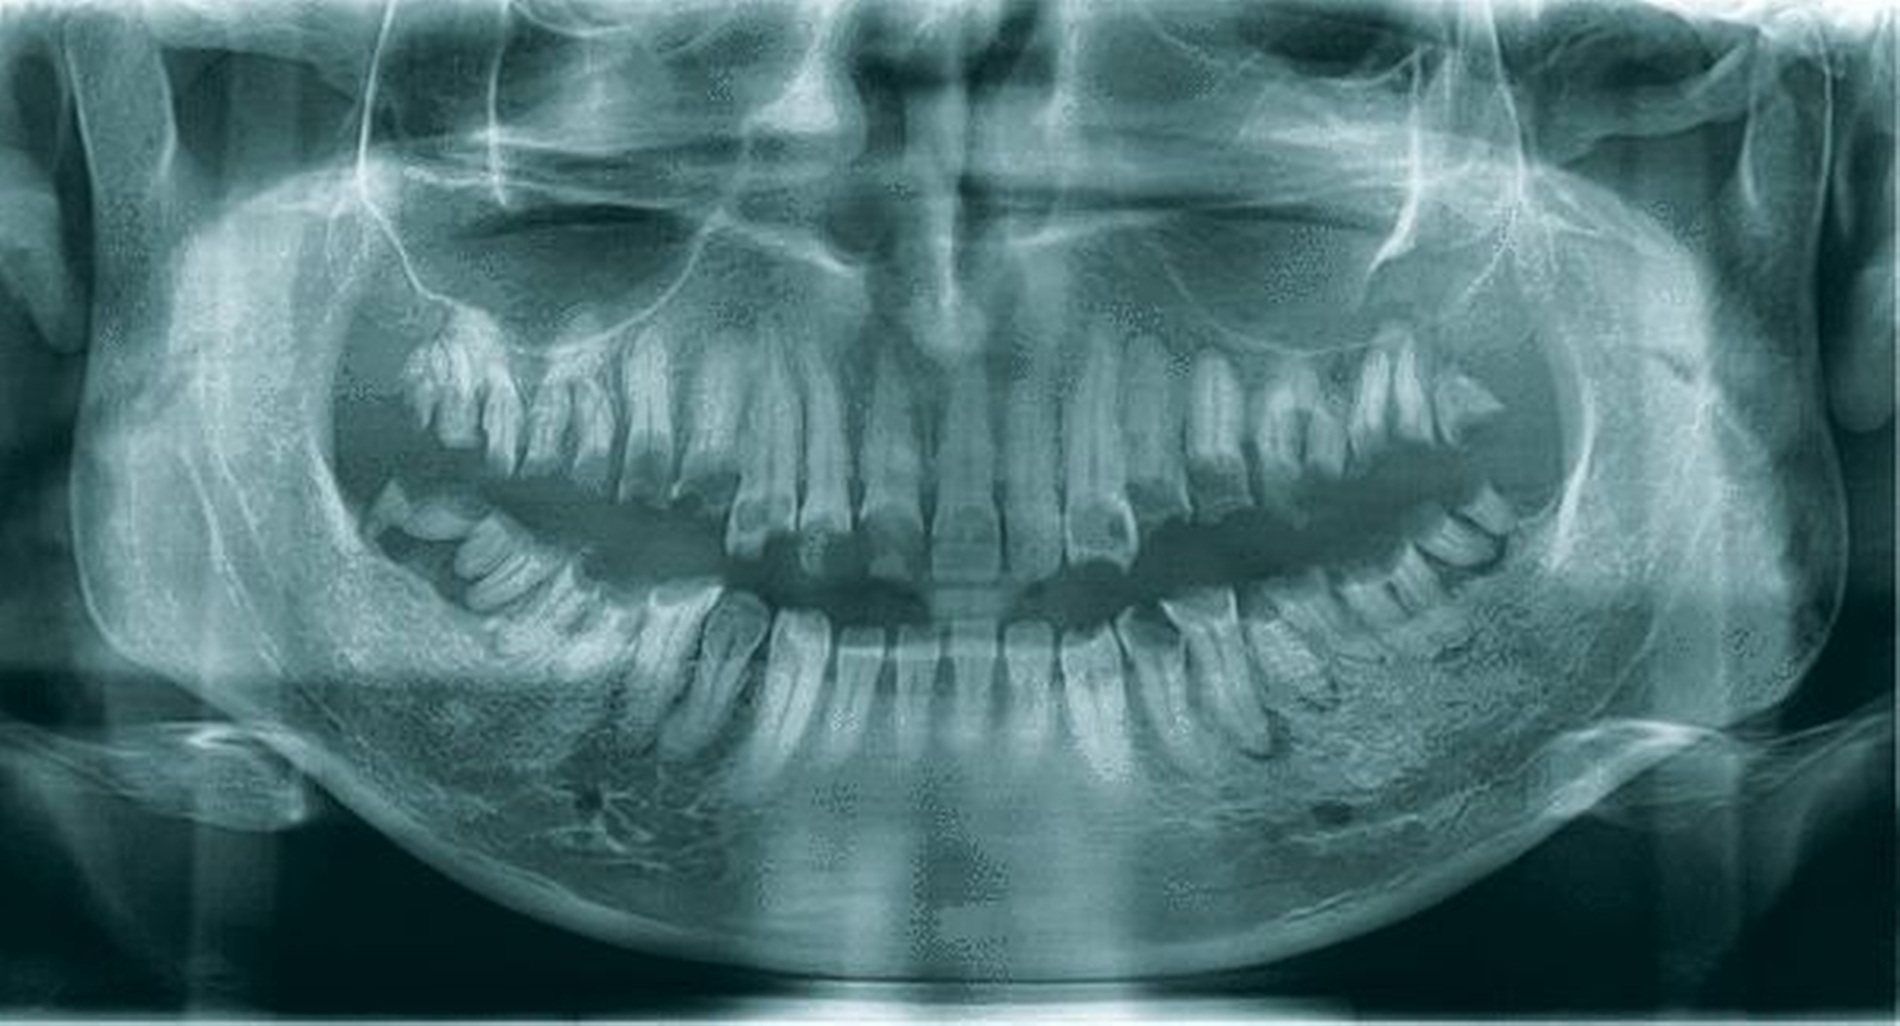

Das OPG (Abbildung 2) zeigte kariöse Defekte an allen Zahnkronen sowie periapikale Osteolysen von 18–15, 24–28, 38–34 und 44–48. Die Zähne 13–23 wiesen kariöse Defekte mit Beteiligung der Pulpa auf. An den Unterkieferfrontzähnen waren keine größeren Defekte oder apikale Aufhellungen zu erkennen.